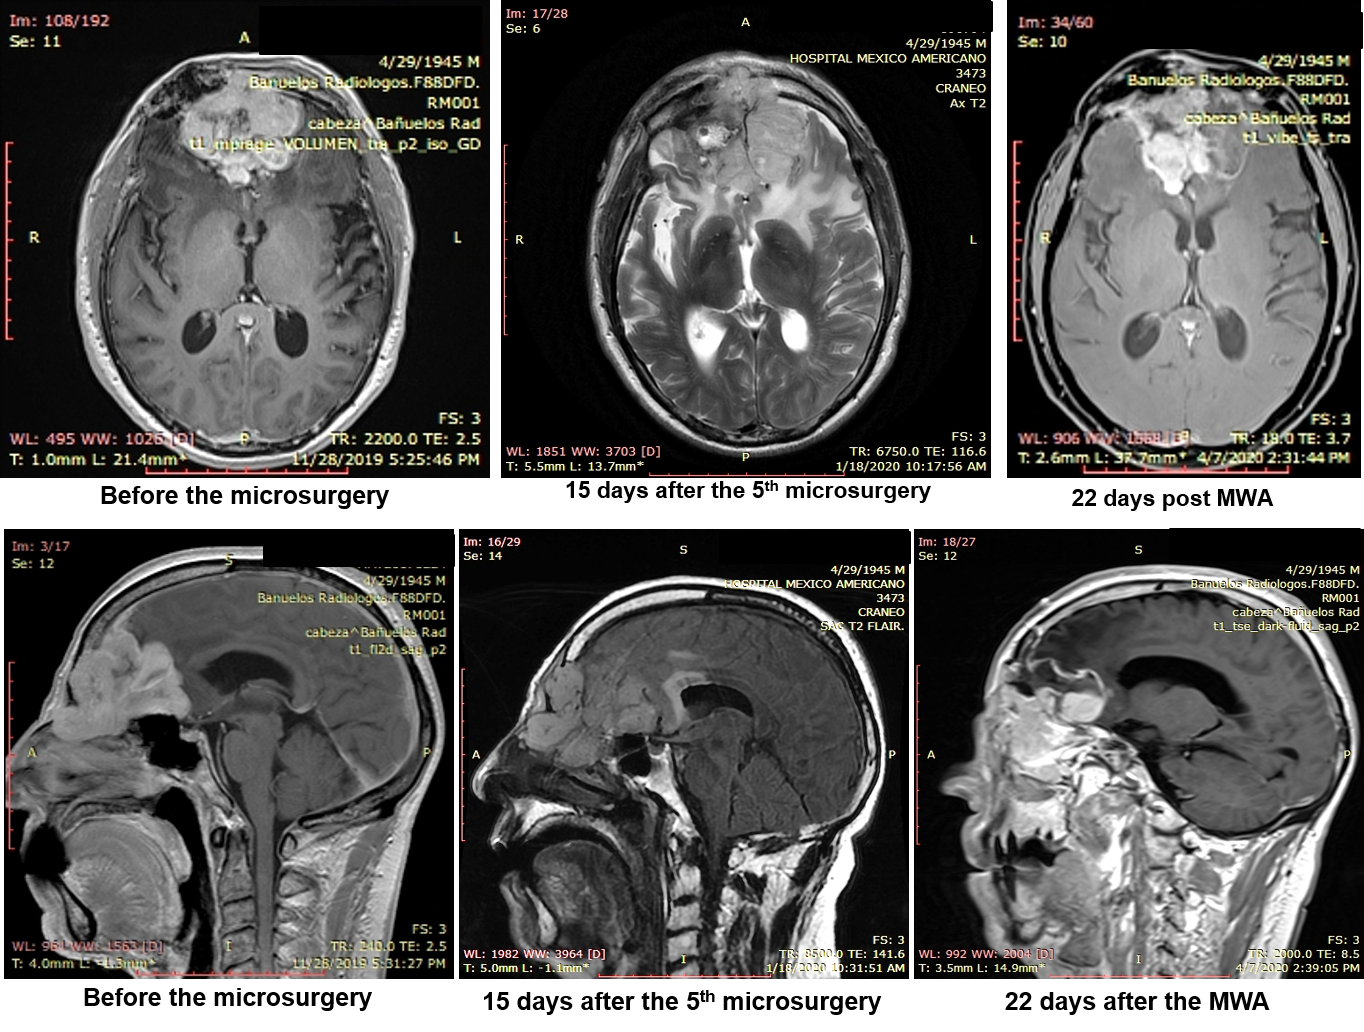

Doctor Santana, a neurosurgeon and his fellows at a major hospital in Guadalajara, Mexico has successfully treated a patient with recurrent malignant meningioma with microwave ablation. The patient had previously failed five (5) surgeries and full dosage of radiation.

Following the failure of the 5th surgical attempt and 30 days in the hospital, microwave ablation (MWA) system developed MedWaves, Inc., San Diego, CA was used to treat the patient. The patient was discharged from the hospital on the 8th day following the MWA with Karnofsky score of 90, which means; he can carry out normal activity with minor symptoms. The magnetic resonance imaging prior to discharge showed significant tumor volume reduction resulting from the MWA. The patient continues to improve and currently being considered for additional intervention with MWA to remove nasal obstruction and pain in the eyes.